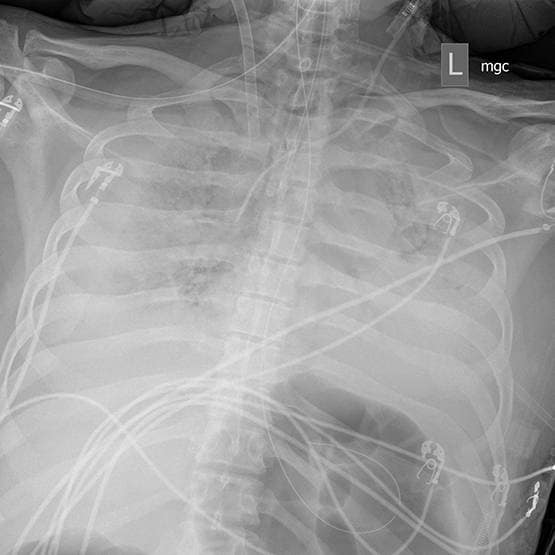

तीन बच्चों के पिता जिम बेलो का इलाज मैसाचुसेट्स जनरल हॉस्पिटल में किया गया. मार्च के शुरुआत में उन्हें तेज फीवर हो गया था. उन्हें 32 दिन तक वेंटिलेटर पर रखा गया. इस दौरान 9 दिन तक उन्हें आर्टिफिशियल हार्ट-लंग मशीन के सहारे जीवित रखा गया. (प्रतीकात्मक फोटो)

जिम बेलो के फेफड़े ने काम करना लगभग बंद कर दिया था. डॉक्टर ने उनके फेफड़ों का एक्सरे देखकर कहा था कि उन्होंने अब तक जितने एक्सरे देखे हैं, यह सबसे खराब है.

पत्नी से मुलाकात के सिर्फ तीन दिन के बाद एक्सरे में डॉक्टरों को उम्मीद की पहली किरण नजर आई. इसके बाद जिम बेलो की हालत लगातार बेहतर होने लगी. आखिरकार 14 अप्रैल को जिम बेलो को वेंटिलेटर से हटा दिया गया और वे खुद सांस लेने लगे. अब वे अपने घर भी लौट आए हैं. (प्रतीकात्मक फोटो)